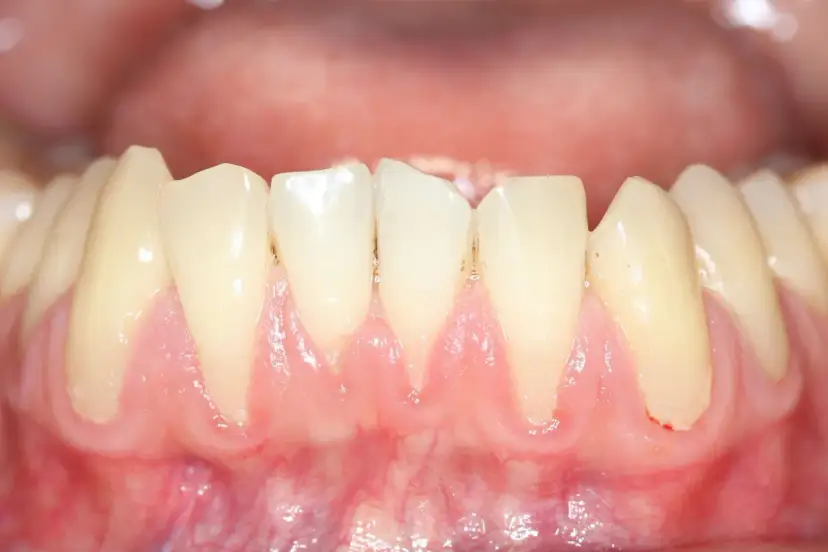

Paradontoza: Kiedy zęby wypadają? Poznaj objawy zaawansowanej choroby i skuteczne metody leczenia, by uratować swój uśmiech. Sprawdź, co możesz zrobić!